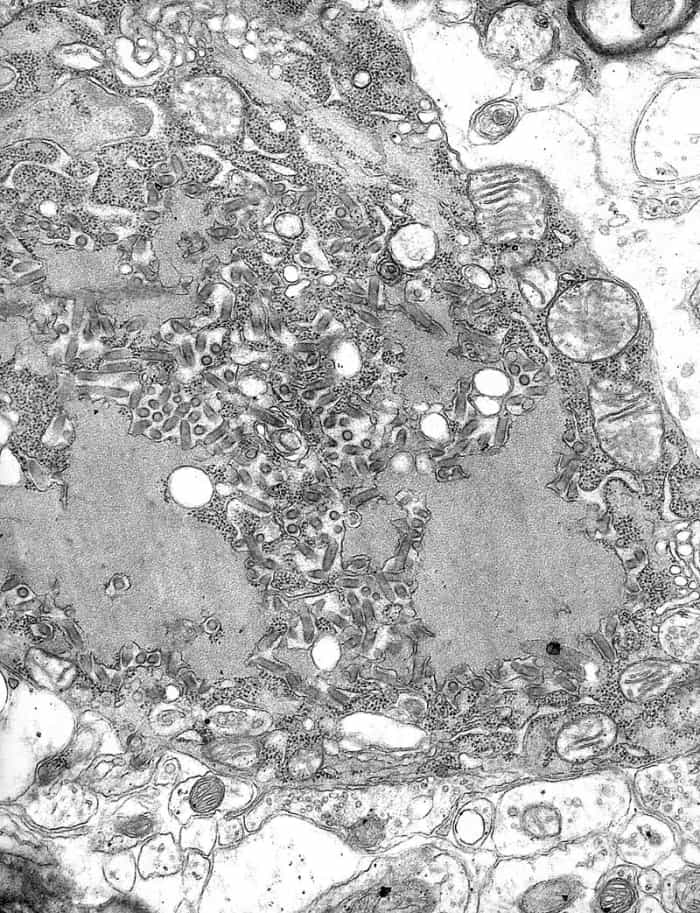

HIV is a life-threatening virus, and is spread via bodily fluids. Upon entering the human body, the virus attack’s the body’s immune system, destroying CD4 cells (also known as T-Cells). The virus progresses through three different stages that include: Acute HIV infection (Stage 1), Clinical Latency (Stage 2), and finally, Acquired Immunodeficiency Syndrome [AIDS] (Stage 3).